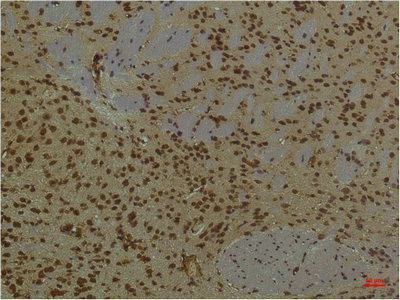

IHC-P analysis of mouse brain tissue using GTX34039 HIF1 beta antibody [4C5].

Dilution : 1:200